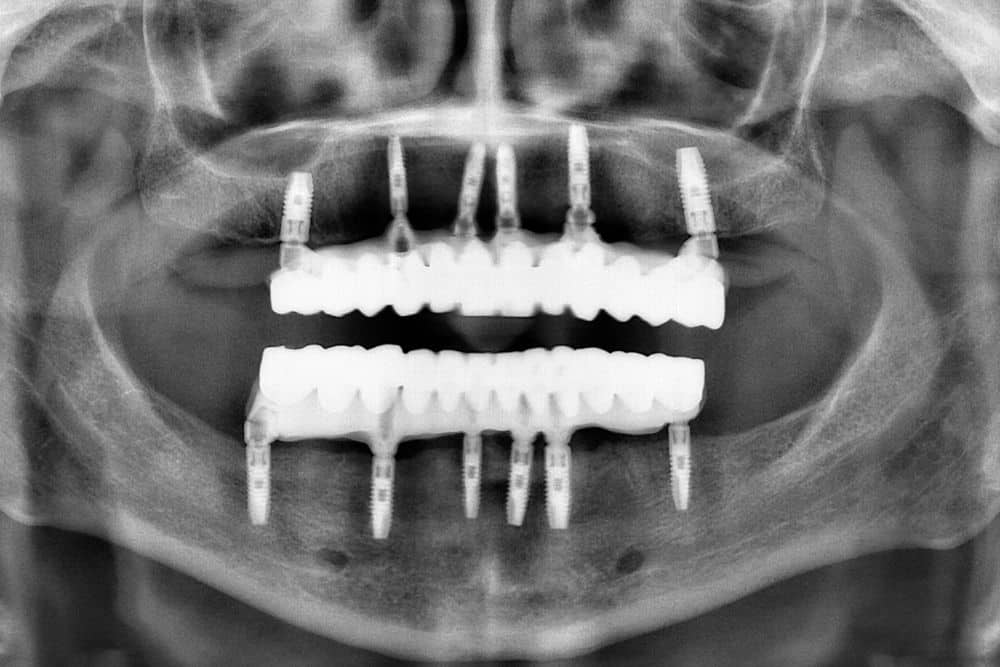

All on 6/ol on siks/ odomaćen je engleski naziv čiji bi prevod glasio „svi zubi na 6 implanata“. Njime se, dakle, označava fiksni protetski rad postavljen na šest implanata ugrađenih u potpuno bezubu vilicu.